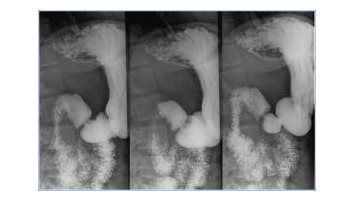

- Rx Transit Oeso-gastro-duodénal